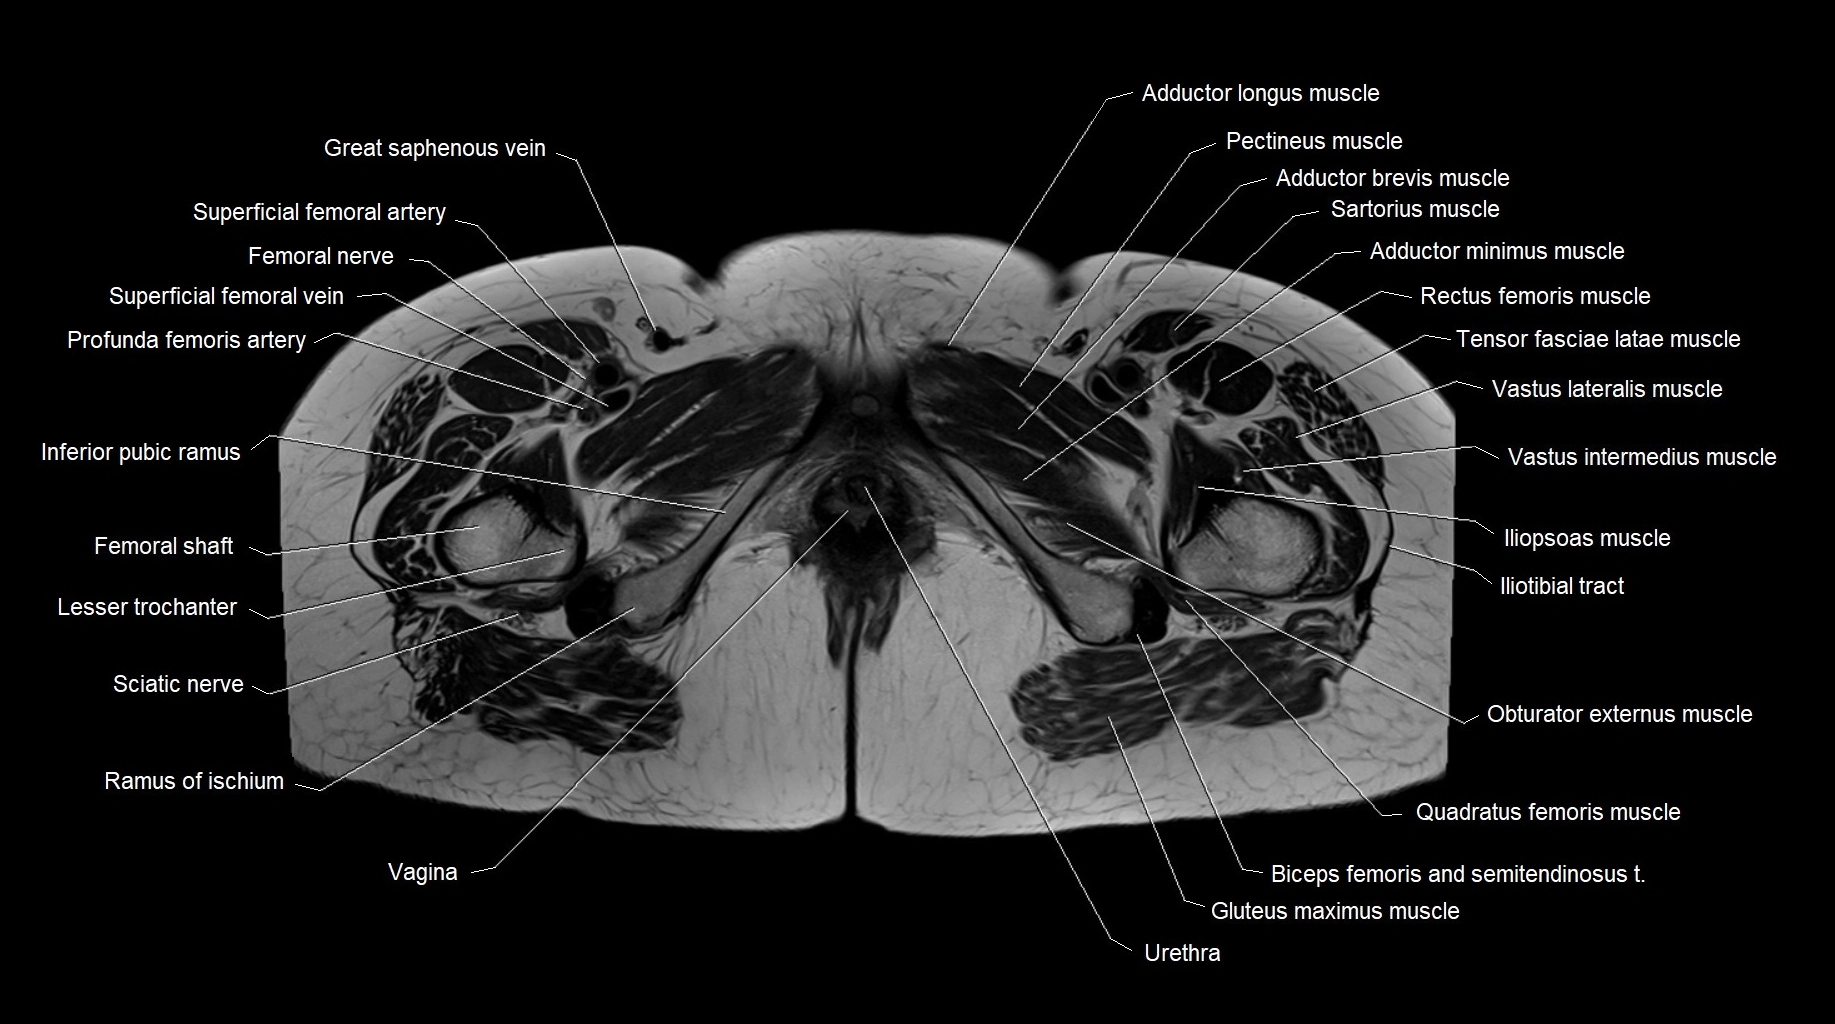

MRI images